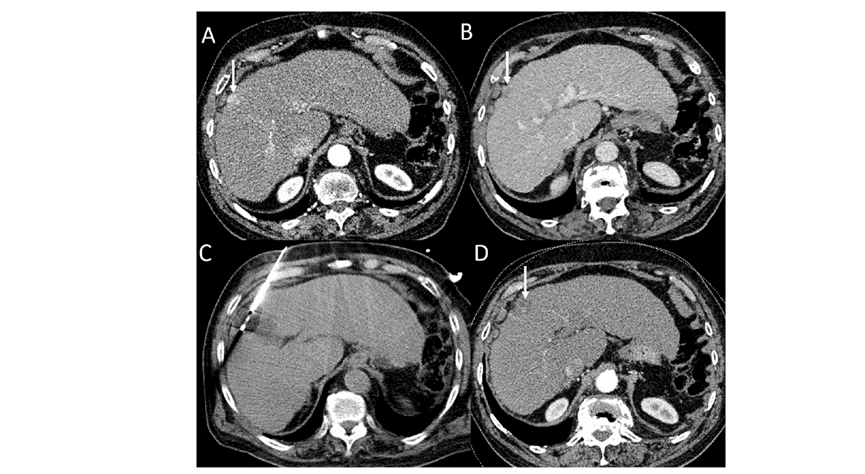

CT引導(dǎo)下冷凍消融

undefined

79 歲男性,肝轉(zhuǎn)移(結(jié)直腸癌)腫瘤的完全消融病例

( a ) 軸向 MRI 和 ( b ) 軸向 CT 顯示肝S8段有一個(gè)16mm的病灶,鄰近肝緣。

( c )冷凍消融期間CT顯示放置了2個(gè)冷凍探針,低密度冰球包圍病灶。

(d)術(shù)后1個(gè)月隨訪 CT顯示冰球?qū)?yīng)的壞死區(qū)域,未見復(fù)發(fā)。

(e)術(shù)后6個(gè)月的CT,壞死區(qū)域縮小,未見復(fù)發(fā)。

(f)與基線影像(g)相比,12個(gè)月后的FDG-PET/CT顯示未見FDG攝取。